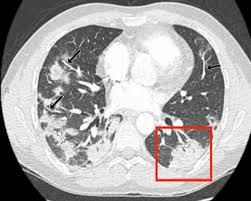

It is sometimes called computerized tomography or computerized axial tomography (cat). I was told that a bone scan is often used for diagnosis whereas ct scans can be used for follow up scans. This test is done because it is common for breast cancer to metastasize to the lungs. Study the brain, spine, chest, abdomen or pelvis find out the size, shape and location of tumours How do ct scans work? When the doctor knows this, they can choose the best course of treatment and maybe even predict your chances of recovery. Metastatic patterns and their prognosis. A trained radiologist will interpret the ct scan images and send the detailed results. If you have a large breast cancer, your doctor may order a ct scan to assess whether or not the cancer has moved into the chest wall. Do ct scans detect breast cancer? Right now, ct scans aren't routinely used to look for breast cancer, but may be used to look at chest, spine, or abdominal problems, such as a herniated disc or lung disease. Benefits of a ct scan. Cas article google scholar 6.

It can damage the dna in your cells and raise the chance that they'll turn cancerous. Additionally, a diagnostic scan only tells part of the story. Metastatic patterns and their prognosis. This test is most often used to look at the chest and/or belly (abdomen) to see if breast cancer has spread to other organs. How do ct scans work? A chest ct scan can detect even smaller nodules in the lung. A ct scan may be done to: Cas article google scholar 6. Scans give doctors the ability to diagnose lung cancer in the earliest stages, which allows for a better cure rate. Ct scans can help doctors: If you have a large breast cancer, your doctor may order a ct scan to assess whether or not the cancer has moved into the chest wall. Ct scans can show a tumor's shape, size, and location. Learn the stage of your cancer.

Other names for this test: A ct scan can help detect a wide range of abnormalities or disease, including cancer, in any part of the body. Scans give doctors the ability to diagnose lung cancer in the earliest stages, which allows for a better cure rate. Ct scans can help doctors: Ct scans can show a tumor's shape, size, and location. The value of preoperative staging chest computed tomography to detect asymptomatic lung and liver metastasis in patients with primary breast carcinoma. I also had a follow up chest ct scan with dye a few months after leaving hospital. Knowing the stage helps your doctor decide which treatment you need. A ct scan may be done to: It can damage the dna in your cells and raise the chance that they'll turn cancerous. Ct scans are most often an outpatient procedure. If your doctor is concerned that you may have a tumor or metastases in your lungs, a better test is a chest computed tomography (ct) scan. The scan is painless and takes about 10 to 30 minutes.